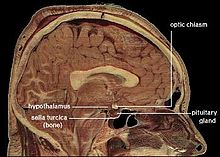

- The hypothalamus is a small region at the base of the forebrain, whose complexity and importance belies its size. It is composed of numerous small nuclei, each with distinct connections and neurochemistry. The hypothalamus regulates sleep and wake cycles, eating and drinking, hormone release, and many other critical biological functions.

A key component of the arousal system is the suprachiasmatic nucleus (SCN), a tiny part of the hypothalamus located directly above the point at which the optic nerves from the two eyes cross. The SCN contains the body's central biological clock. Neurons there show activity levels that rise and fall with a period of about 24 hours, circadian rhythms: these activity fluctuations are driven by rhythmic changes in expression of a set of "clock genes". The SCN continues to keep time even if it is excised from the brain and placed in a dish of warm nutrient solution, but it ordinarily receives input from the optic nerves, through the retinohypothalamic tract (RHT), that allows daily light-dark cycles to calibrate the clock.

In vertebrates, the part of the brain that plays the greatest role is the hypothalamus, a small region at the base of the forebrain whose size does not reflect its complexity or the importance of its function. The hypothalamus is a collection of small nuclei, most of which are involved in basic biological functions. Some of these functions relate to arousal or to social interactions such as sexuality, aggression, or maternal behaviors; but many of them relate to homeostasis. Several hypothalamic nuclei receive input from sensors located in the lining of blood vessels, conveying information about temperature, sodium level, glucose level, blood oxygen level, and other parameters. These hypothalamic nuclei send output signals to motor areas that can generate actions to rectify deficiencies. Some of the outputs also go to the pituitary gland, a tiny gland attached to the brain directly underneath the hypothalamus. The pituitary gland secretes hormones into the bloodstream, where they circulate throughout the body and induce changes in cellular activity.